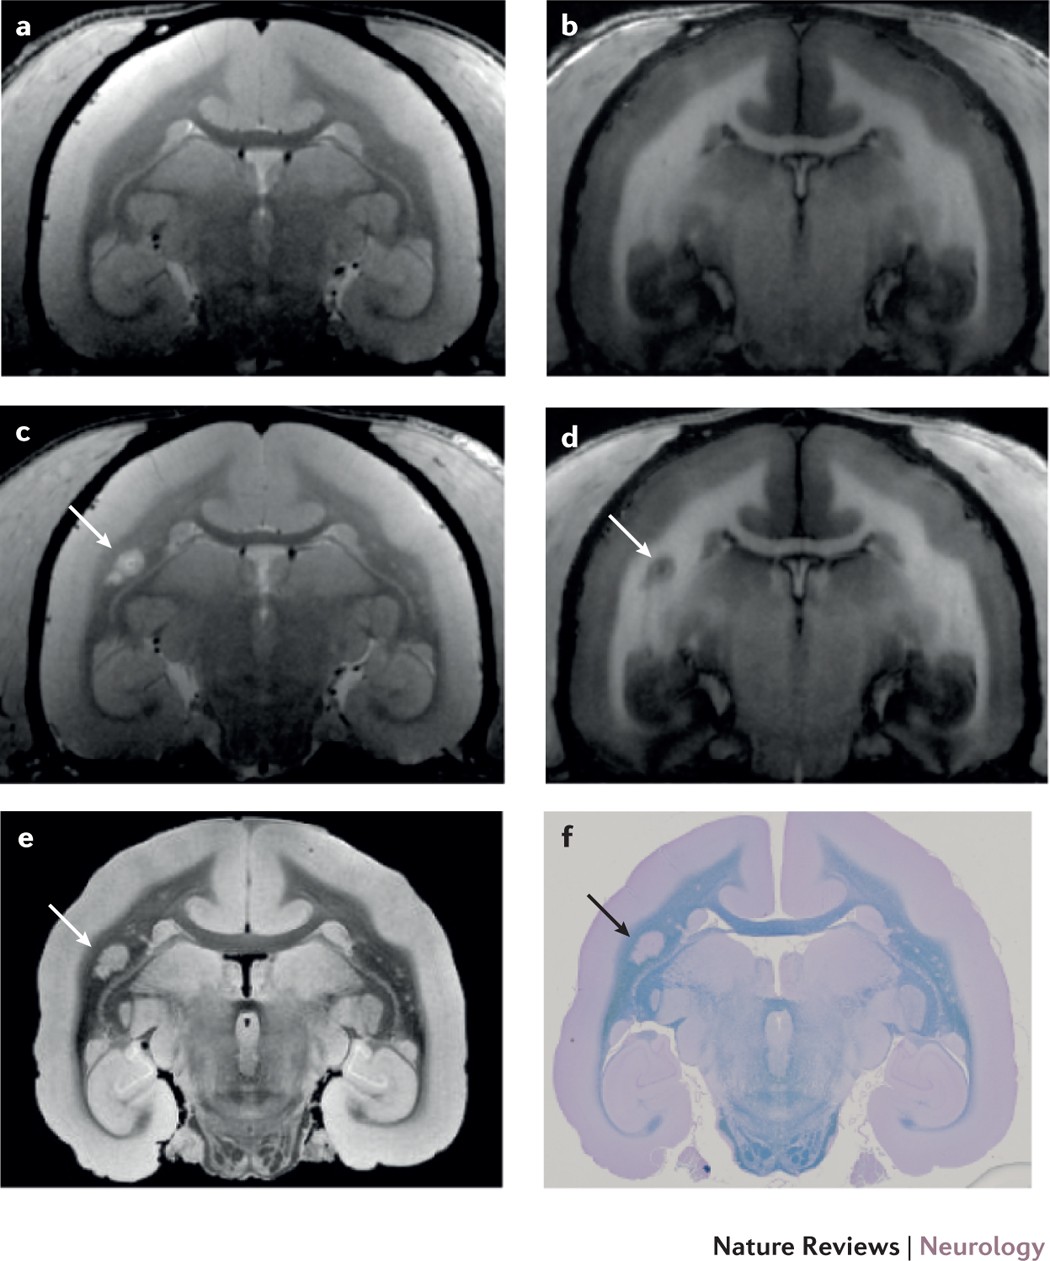

Advanced Mri And Staging Of Multiple Sclerosis Lesions Nature Reviews Neurology